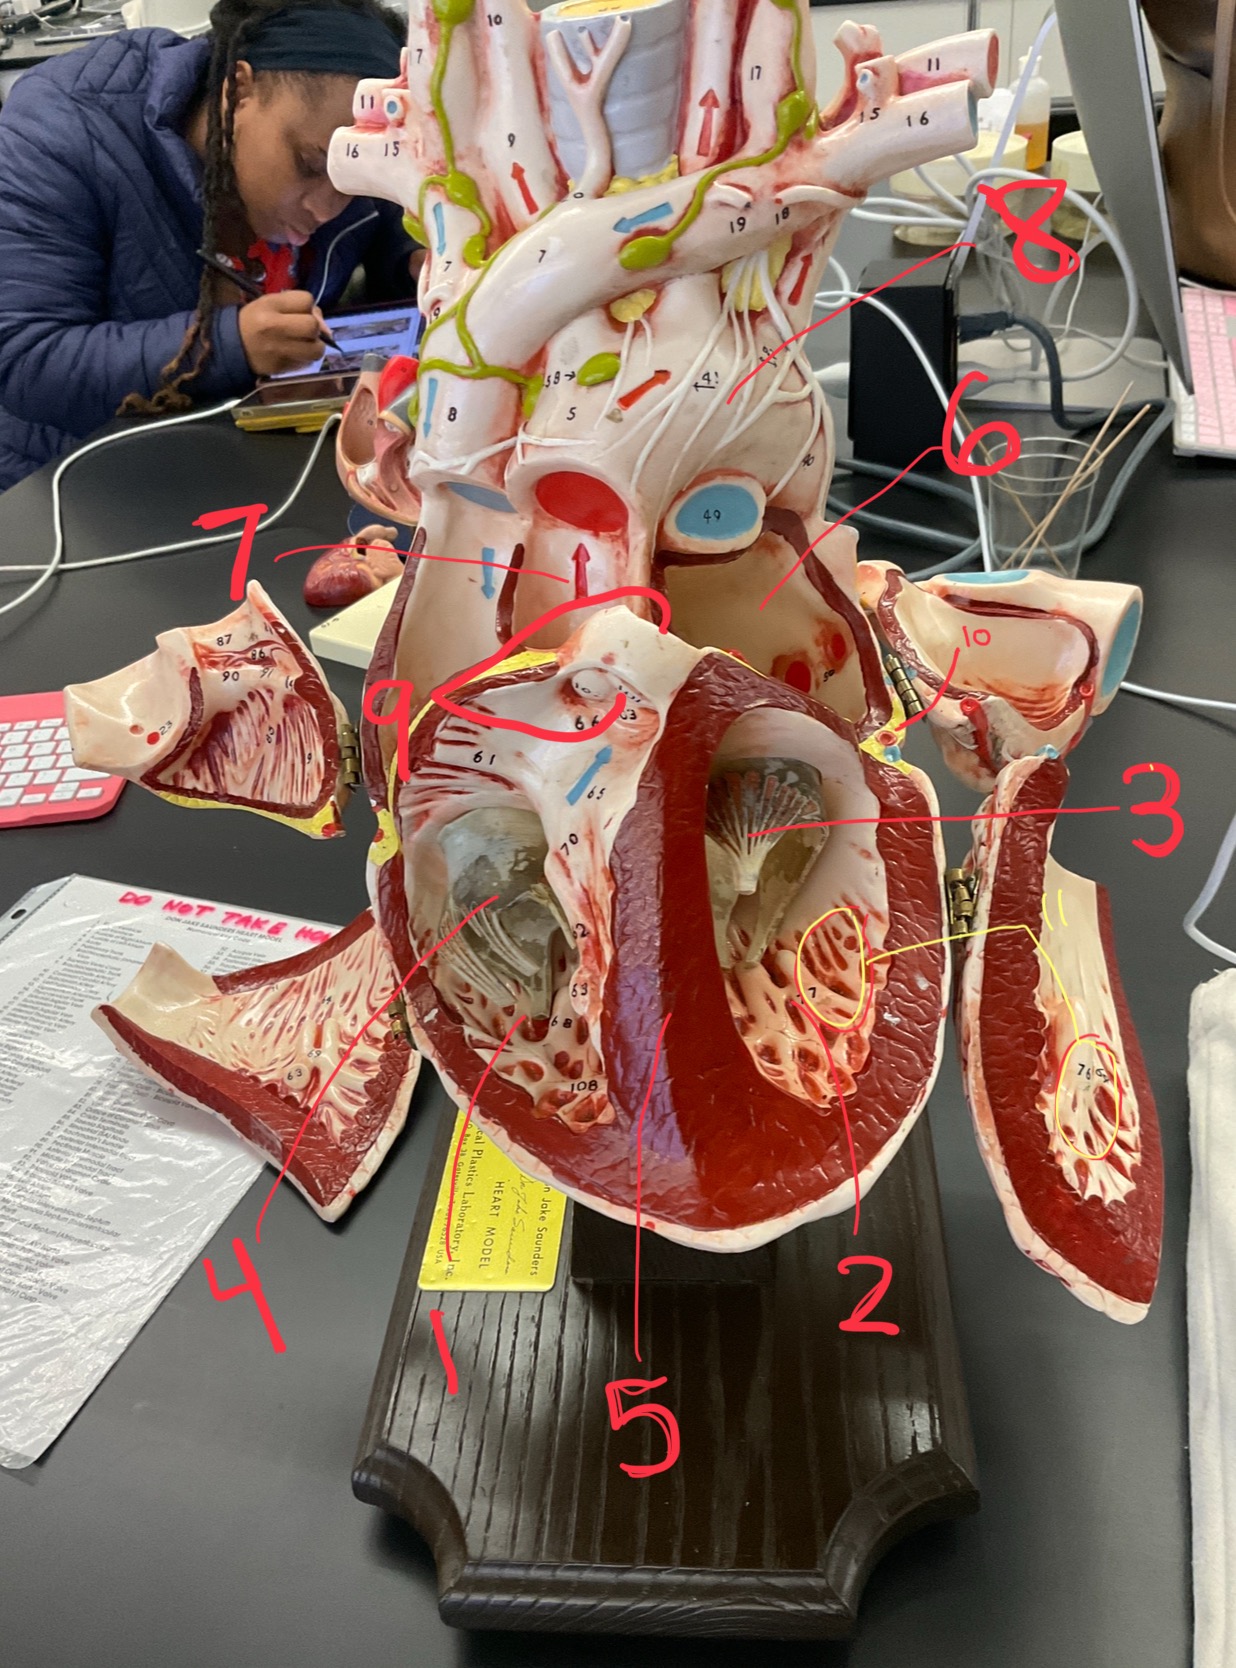

1

epicardium

2

3

endocardium

3

2

myocardium

4

1

coronary sinus

5

2

inferior vena cava

6

3

superior vena cava

7

1

right ventricle

8

2

left ventricle

9

3

bicuspid

10

4

tricuspid

11

5

interventricullar septum

12

6

left atrium

13

7

aorta

14

8

aortic trunk

15

9

pulmonary semi-lunar valve

16

10

atrevoventricullar sulus

17

11 (not smooth part)

trubeculae carneae

18

1

papillary muscle

19

2

chordae tendineae

20

4

pulmonary trunk

21

6

aortic trunk